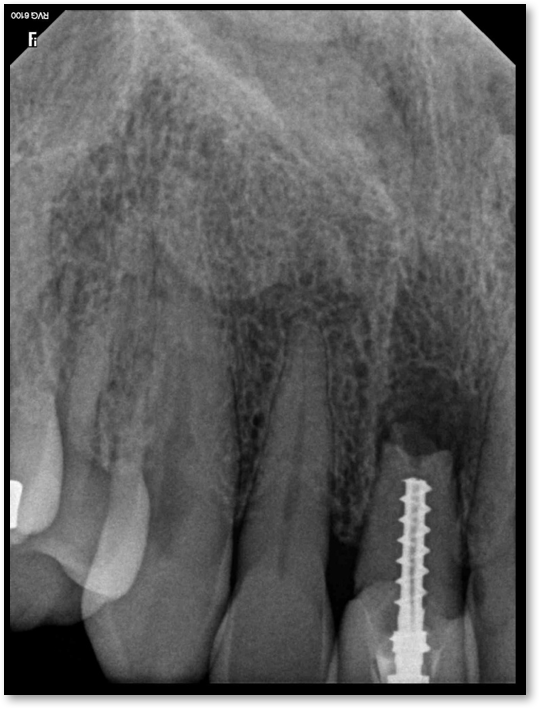

Adjacent Structures

If a tooth stands alone, greater forces will be placed on it because it has no adjacent teeth to provide support. This situation will affect the decision-making process for placing a post. Figure 3 shows a tooth that was on an island and would be having three implants placed in front of it. The tooth would take a much greater beating than another tooth that had support proximally. Even though it had a good root canal, the clinician would need to account for whether the tooth would last until the implants integrated. Figure 4 shows a case that would quickly proceed to implants. The patient had a less-than-ideal bridge for over a decade, with decent endodontics and functionality. There was also an overhang on the premolar. The post was not ideal in this case because there was one distal canal and not all the gutta-percha was removed from it. An intimate fit should be the goal with the post and the walls. Whether using a threaded or non-threaded post, there should not be excess gutta-percha because it is not as solid as the tooth and will lead to greater movement. That movement on the tooth and bridge will create too much force and result in demise.

Fig 3. Tooth on an island.

Figure 3

Fig 4. Case that quickly would proceed to implants.

Figure 4